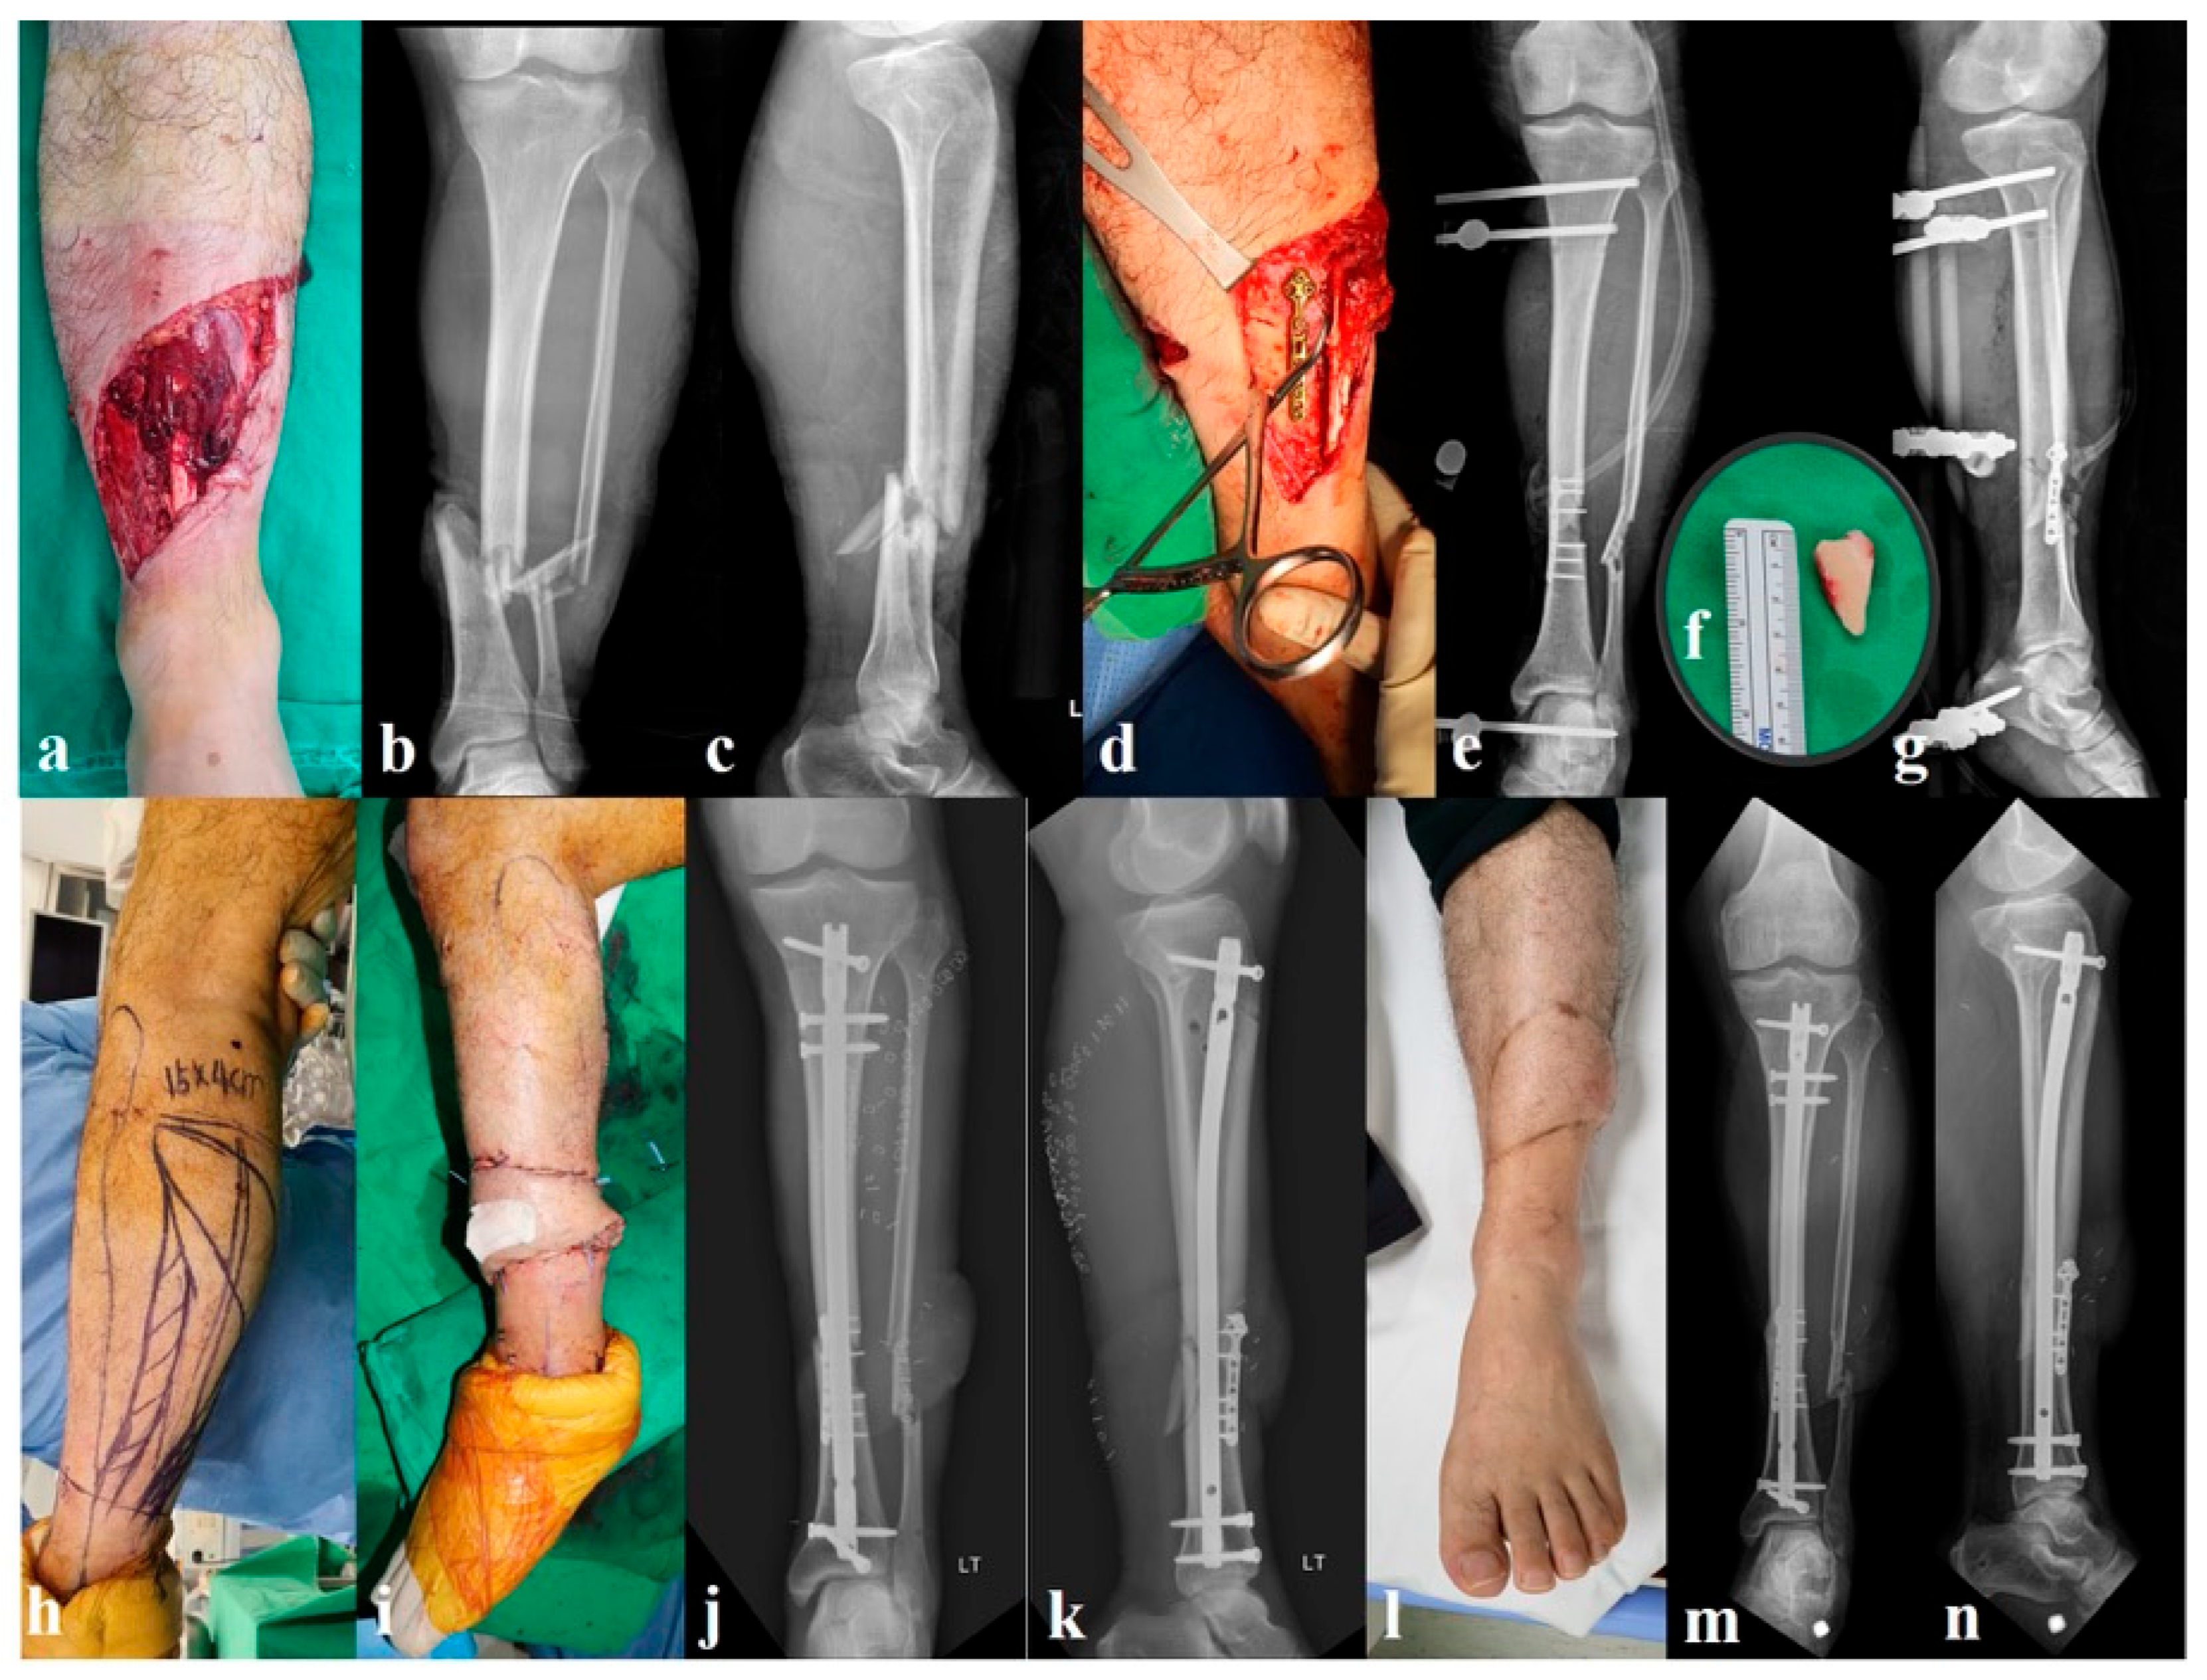

2.2.1. Group A: Provisional Miniplate and External Fixation (n = 32, Figure 1)